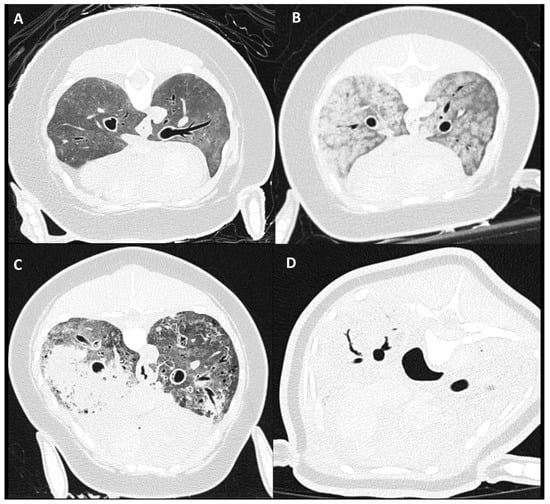

3.4. Pulmonary Parenchymal Attenuation Changes